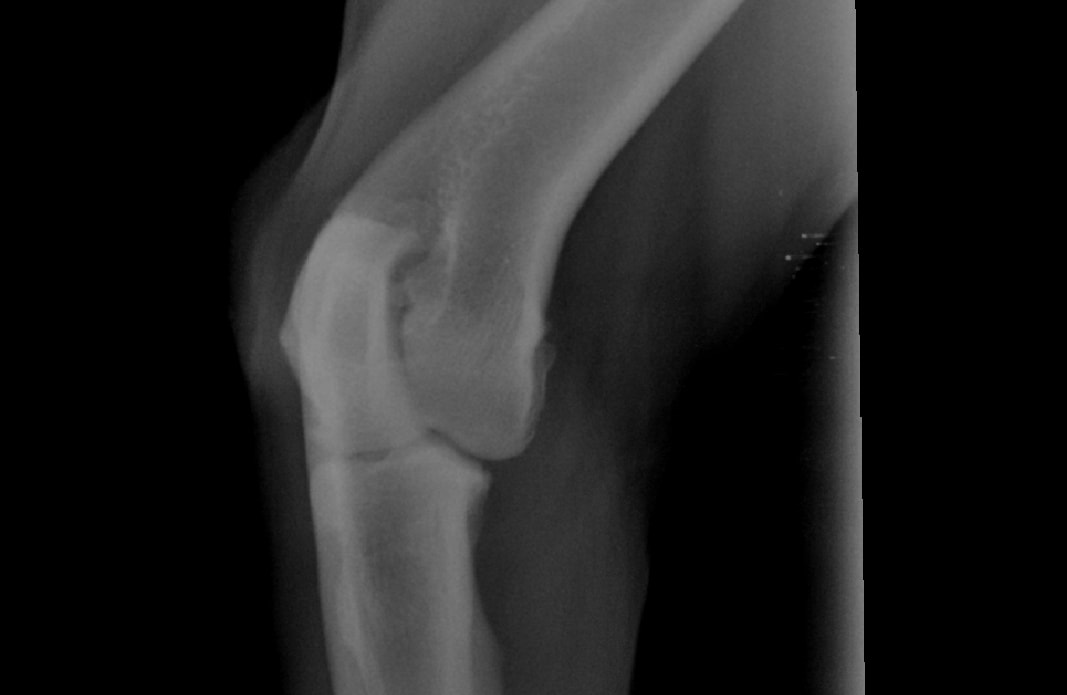

Pet's info: Dog | Rottweiler | Male | neutered | 4 years and 5 months old | 110 lbs

Hi, I recently asked a question on here regarding my dog. we took him for a 2nd opinion regarding his right front leg. they too cannot see what is wrong - the vet suspects bone cancer or broken cartridge in his humorous. All they did was give us anti inflams for 4 weeks and said come back for more xtrays. My question. if it is bone cancer - then Why are they making us wait for it to progress. I have attached the Xrays again. Why have they not done a bone biopsy? this is our 2nd opinion already

I don't see any abnormalities in the radiographs that you show. Bone cancer can occasionally be difficult to diagnose before it is very severe. To biopsy a bone for possible cancer, you need to know where in the bone to sample, so it is not as simple as just picking any part you want. Advanced diagnostics like MRI or CT may be more helpful at looking more closely at the soft tissue (muscles, tendons, ligaments) and bone to see if there are any abnormalities. You will likely need a referral to a specialty hospital for this procedure. If you are concerned about something life-threatening like bone cancer, I would recommend that you speak with either vet about a referral.